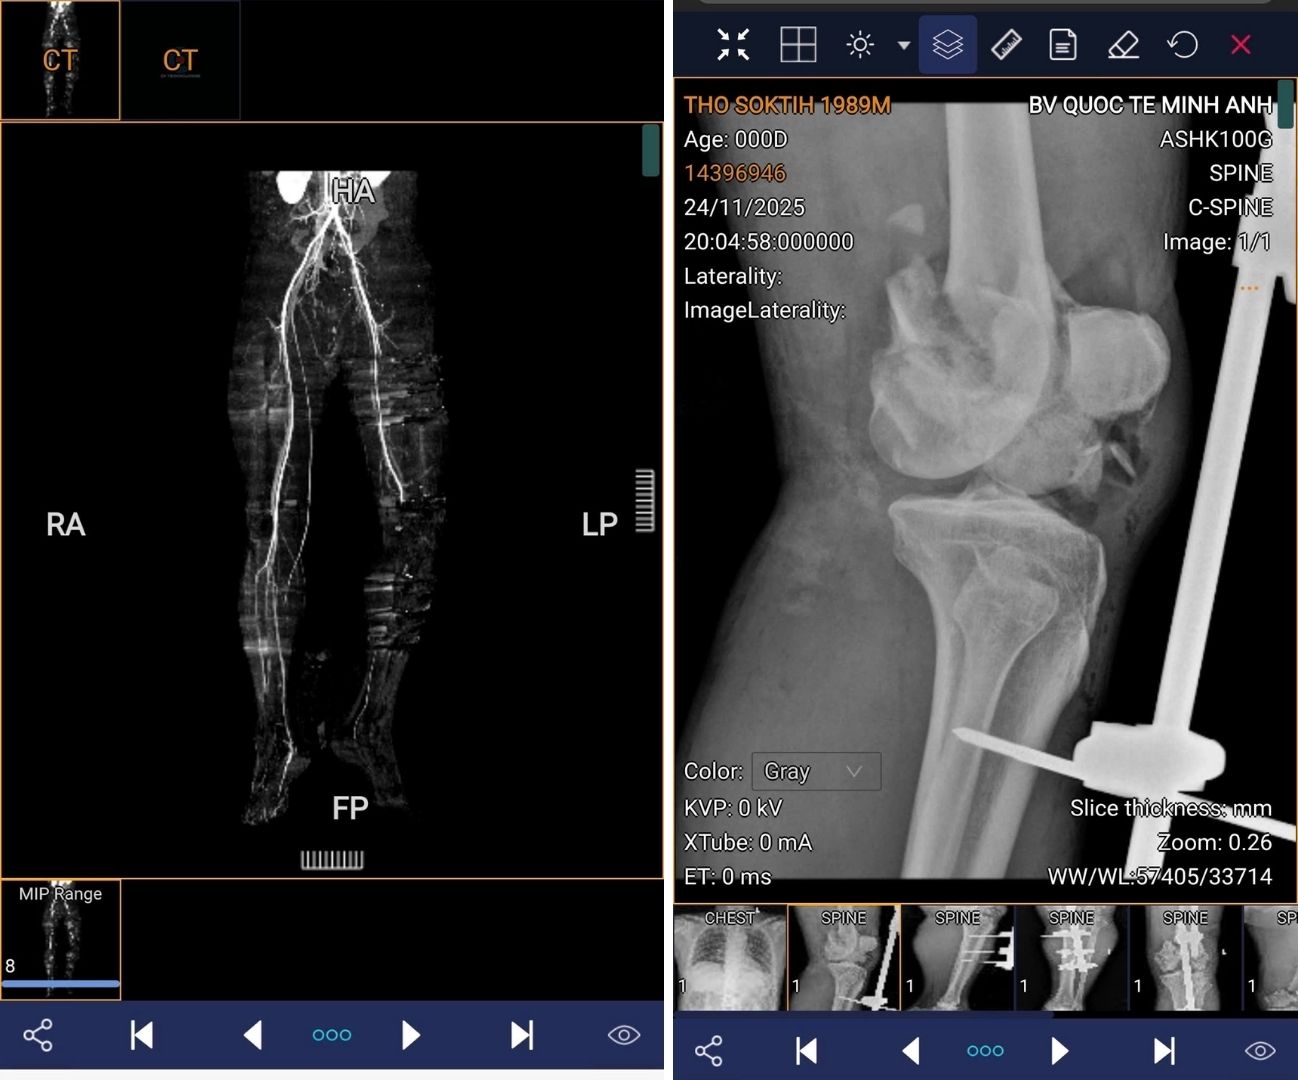

Bệnh nhân là anh N.K.P. (47 tuổi, quốc tịch Campuchia), nhập viện trong tình trạng cấp cứu sau tai nạn giao thông với tổn thương nặng vùng khoeo chân. Khi đến bệnh viện, thời gian từ lúc tai nạn đã trôi qua 22 giờ, trong khi theo y văn, “giờ vàng” để cứu một chi thể bị tổn thương mạch máu thường chỉ khoảng 6 giờ. Khám ban đầu ghi nhận khoeo chân bị đụng dập, có vết thương hở; bàn chân trái lạnh, các ngón chân tê nhưng vẫn còn cử động; không bắt được mạch mu chân và mạch chày sau. Trước đó, dù đã được sơ cứu và đặt khung cố định, các bác sĩ tại địa phương đều đưa ra chỉ định cắt cụt chi để bảo toàn tính mạng.

Đứng trước lựa chọn khó khăn giữa cắt bỏ chi để đảm bảo an toàn tính mạng hay mạo hiểm để giữ lại hình hài vẹn toàn cho người bệnh, ê-kíp liên chuyên khoa đã tiến hành thám sát kỹ lưỡng. Khi đánh giá thấy các khối cơ vẫn còn khả năng hồi phục, các bác sĩ quyết định thực hiện phẫu thuật tái thông mạch. BS.CK2 Nguyễn Thành Hưng - Khoa Lồng ngực - Mạch máu, cho biết động mạch khoeo của bệnh nhân đã đứt rời hoàn toàn, mất đoạn dài hơn 2 cm, không thể nối trực tiếp. Ê-kíp buộc phải sử dụng kỹ thuật vi phẫu, lấy tĩnh mạch hiển tự thân ở chân lành để làm mảnh ghép bắc cầu, nối lại dòng máu nuôi chi dưới.